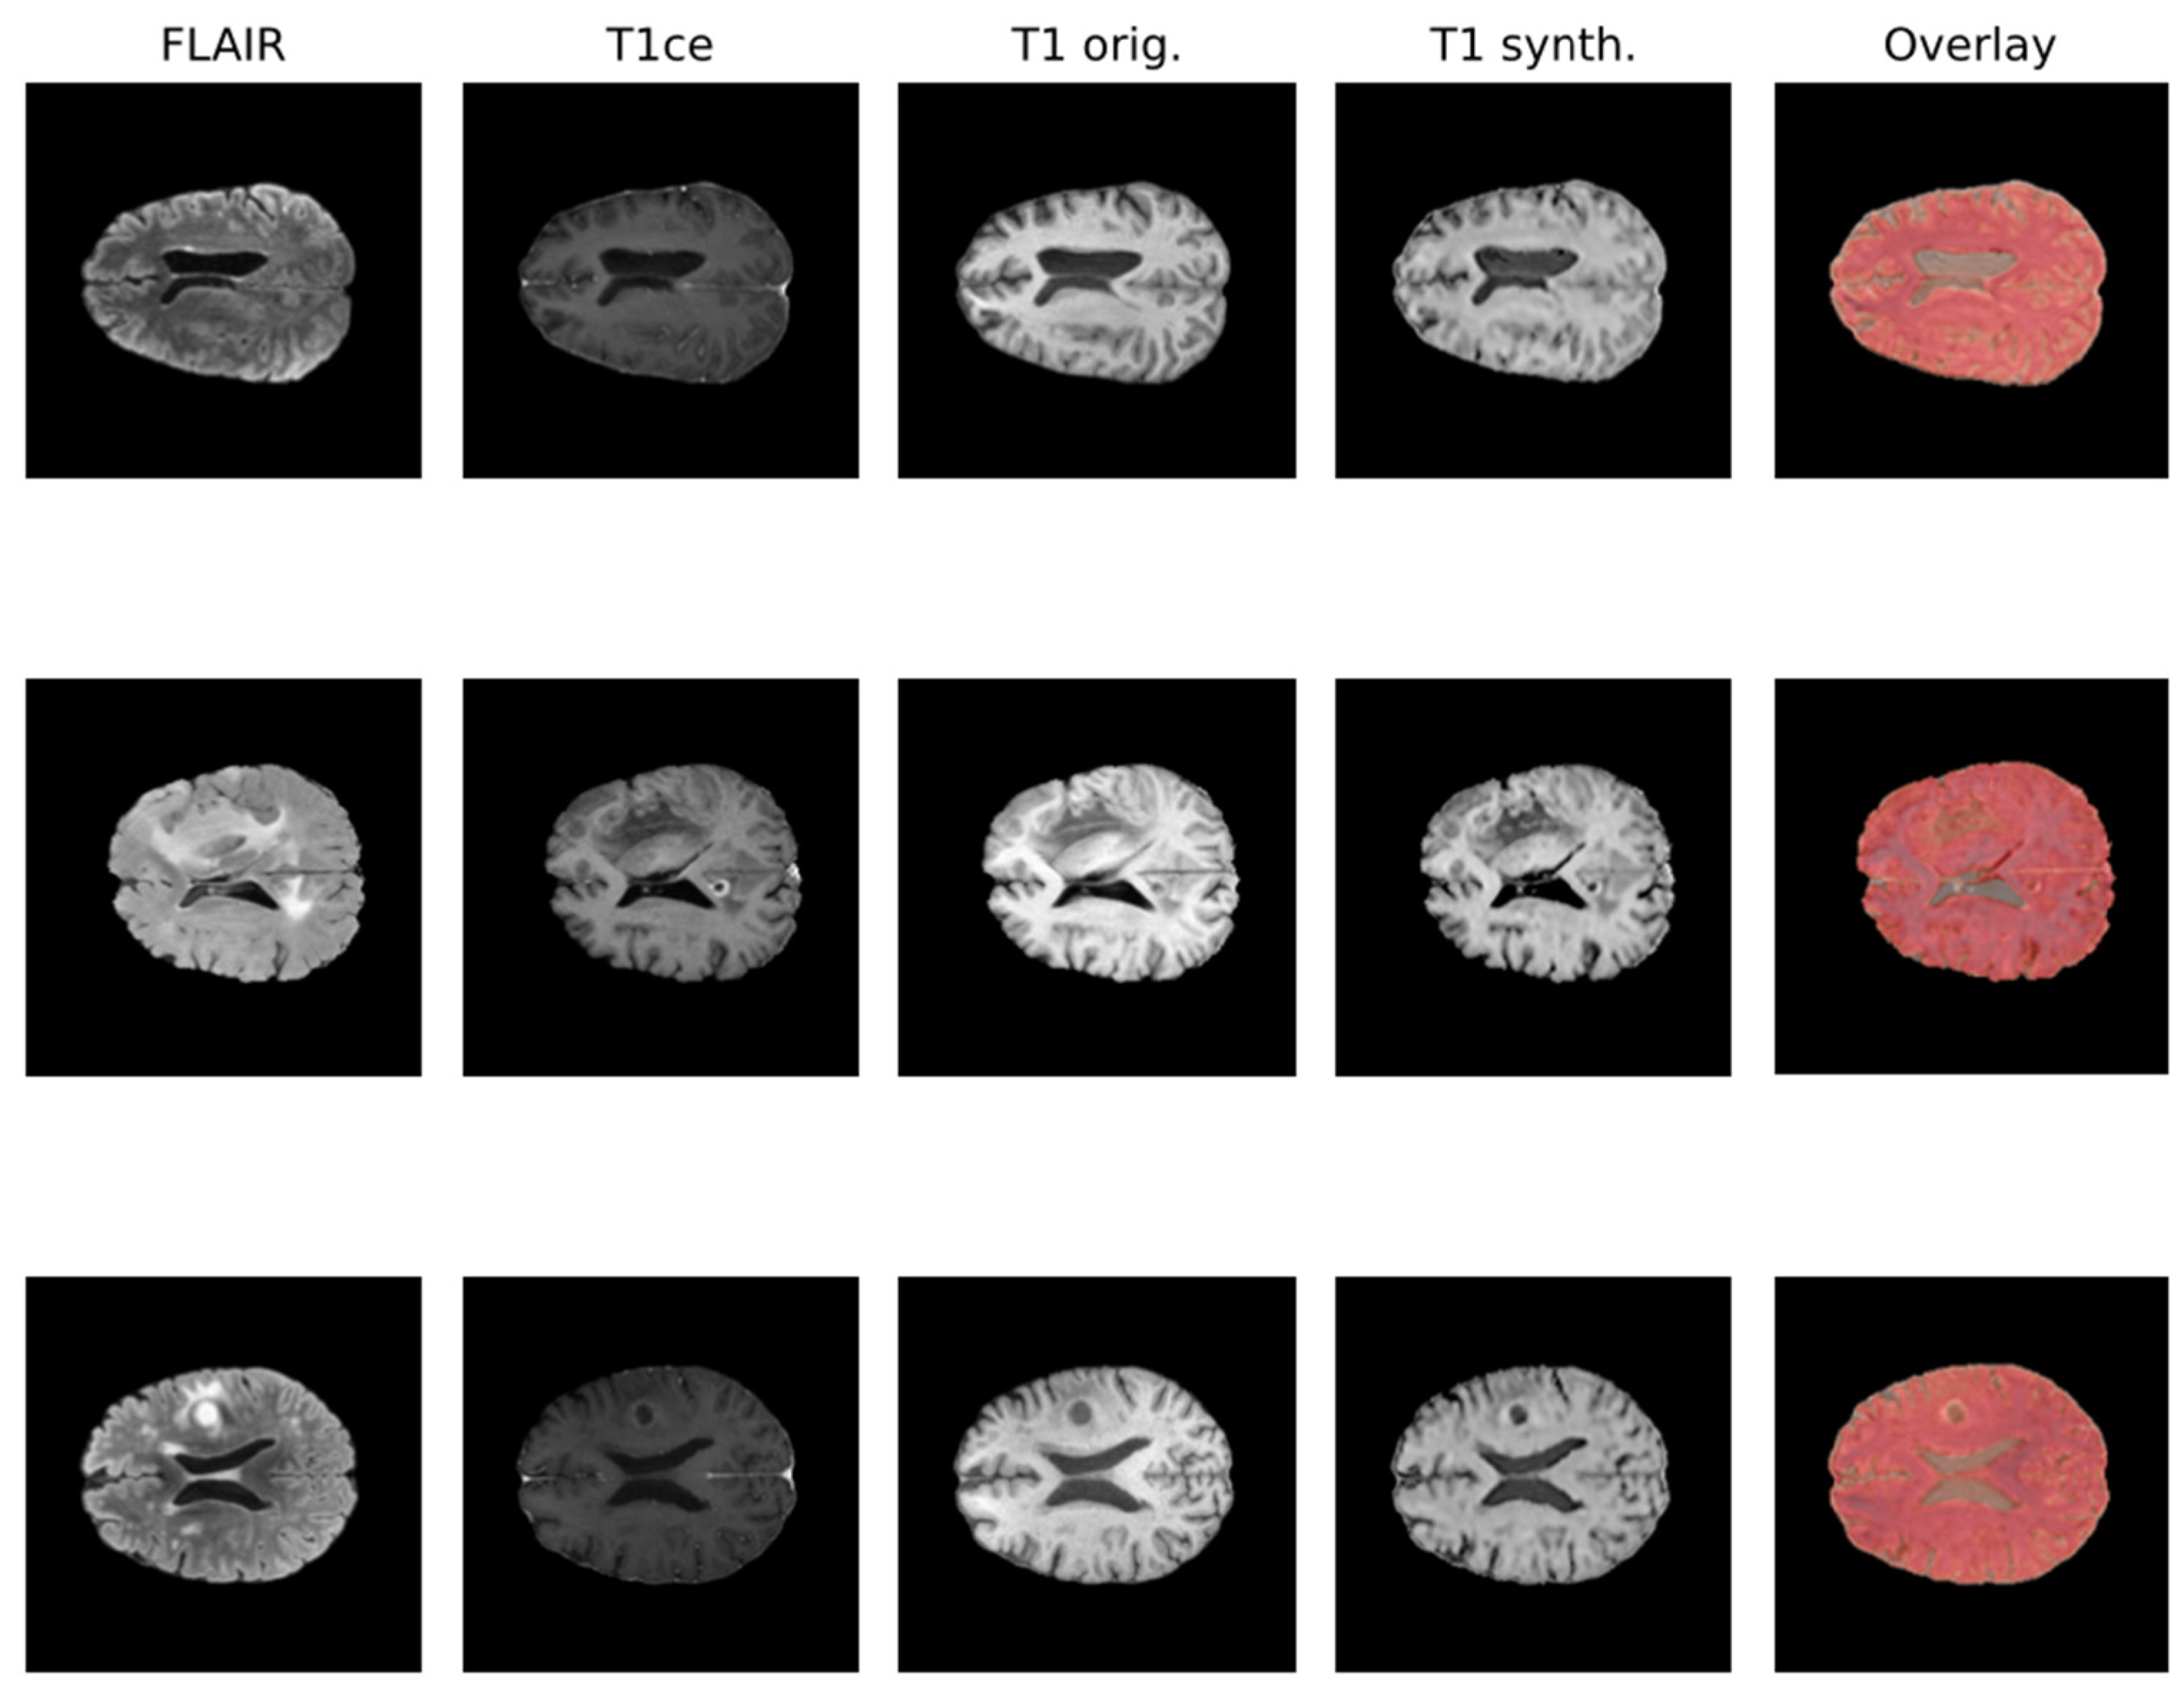

Due to the rise in deep learning, image synthesis within the same modality (such as intramodalities: e.g., from MRI to CT) and across modalities (intermodality: e.g., from FLAIR MRI to T1ce MRI), which entails artificially reconstructing missing sequences from available ones, has attracted considerable attention. This area is emerging as a vibrant and promising research domain. In Figure 1, the IMT model proposed by Osman et al. [27], which was able to generate an accurate synthesis result by generating the missing modalities, is shown.

Figure 1.

Qualitative comparison of synthesized T1 scans from BraTS 2021 dataset using the IMT technique.

Various network architectures have been proposed for such tasks in medical imaging within the last few years, but three main backbone models achieved the best results: autoencoder, U-Net, and GAN, with the first starting to lose pace compared to the others [26]. Some studies specifically tackled the problem of brain MRI intramodality synthesis. Yang et al. [28] proposed a method to perform image modality translation (IMT) by leveraging conditional generative adversarial networks (cGANs), whose generator follows the U-Net shape by adding skip connections between mirrored layers in the encoder–decoder network and whose discriminator is derived from a PatchGAN classifier. Osman and Tamam [27] instead implemented a U-Net model aimed at learning the non-linear mapping between a source image contrast to a target image contrast.